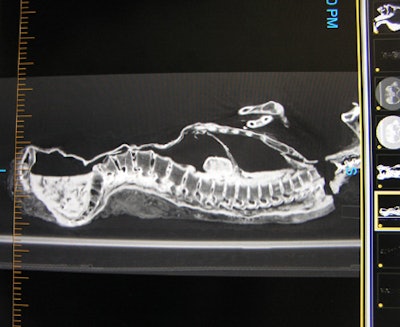

![]() |

| Above: The thoracic and pelvic regions of the mummy. Below: A lateral view of the regions. Bottom: The pelvis and legs. Images courtesy of Michelle Cotton, Advanced Radiology Consultants. |

One of the most surprising findings on the CT data is that the mummy appears to be female due to its pelvic structure and signs of arthritis in the area, a possible indication of having given birth, according to experts at Advanced Radiology. Despite the findings contradicting the long-held belief that the mummy was male, the remains could still be those of an Egyptian priest as claimed, as women also held that position, according to Barnum Museum's executive director and curator Kathy Maher.